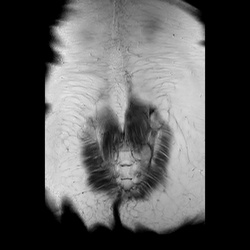

MRI_MYELO_radial_1101

6 photos